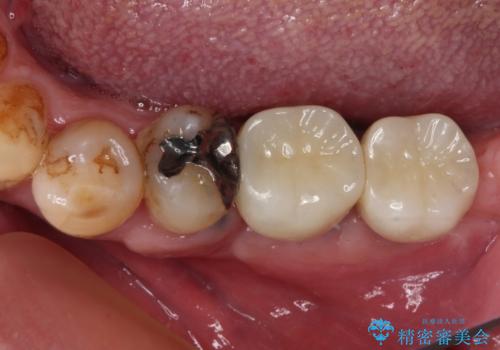

- 抜歯をしたものの、インプラントにするか入れ歯にするか悩んでいるうちに2年以上経過してしまったとのことで来院された患者様です。

自分の歯のように噛めるようにしたいとのことで、インプラントによる欠損補綴治療を行うこととしました。

インプラントにはストローマン社のSLActiveを使用し、埋入から補綴までおよそ3か月と、短期間で治療を進めることができました。